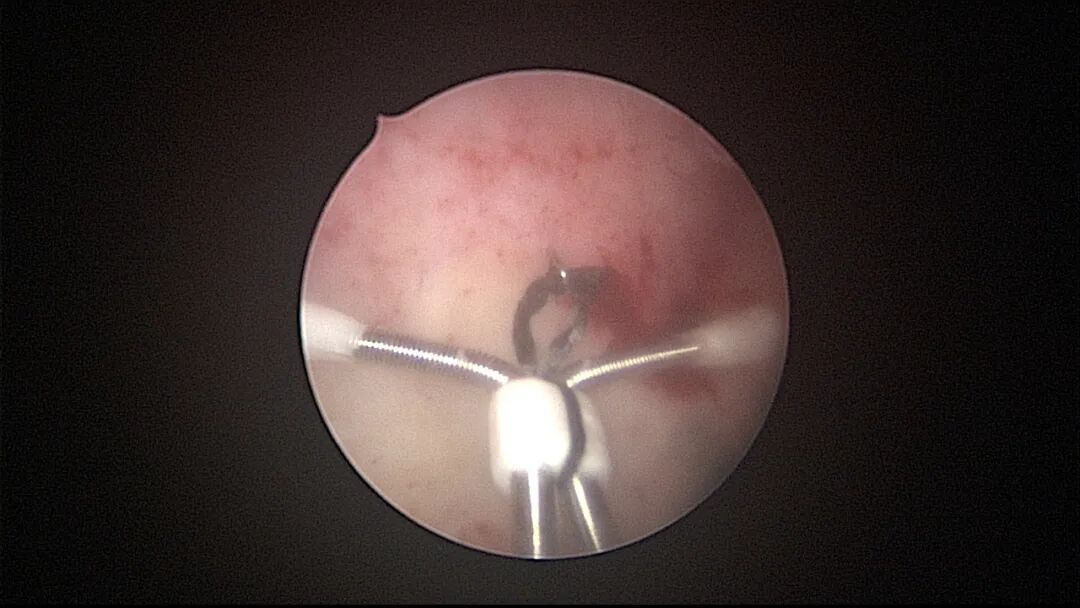

操作步骤描述:宫腔检查镜可完成操作,扩张宫颈至7号扩宫棒,检查镜能轻松通过,避免镜鞘与节育环纵臂在宫颈管形成卡压及筷子效应,影响操作,或卡压摩擦阻力大带出节育环。可用单级电针在宫底扎出小凹坑做标记或作为置入挂钩的隧道(不是必须的)。将挂钩用异物钳直视下送入宫腔,或用中弯钳盲视下送入宫腔,异物钳夹持挂钩将倒钩端插入宫底肌层,越过倒钩。用环尾丝或不可吸收线在节育环顶端打结,形成一个线圈,直径约0.5cm~1cm,结打在线圈旁边,便于夹持操作。将环装回推杆送入宫腔,再夹住节育环固定线圈抵紧宫壁稍旋转就可以将线圈滑进挂钩缺口,挂到挂钩上,可再次向宫底推送挂钩少许,不必夹闭挂钩缺口,重力作用和内膜生长都会阻止线圈脱出,可以用电针电凝挂钩周围组织,进一步防止挂钩脱落。异物钳原位固定节育环,退出宫腔镜,距宫颈外口0.5cm~1cm剪断剩余尾丝。宫颈扩张到9号扩宫棒,冷刀系统异物钳夹持挂钩及线圈也可完成以上操作。

取胚术后丝线挂钩固定节育环图片及视频